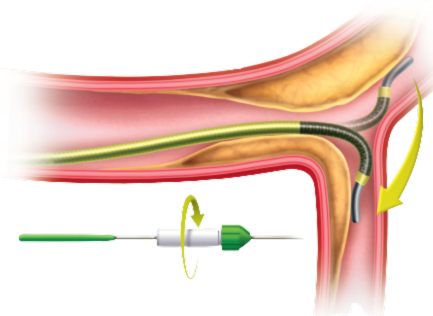

SHAPE IT

TRANSFORMING BIFURCATION ACCESS WITH RX CONVENIENCE

Access to side branches can be challenging. The ShapeIT provides state-of-the-art guidewire support for side branch access. The 180° pre-shaped distal end as well as the most distal two centimeters can be shaped to conform your needs, simplifying guide wire access to side branches. The 1:1 torque response from proximal shaft to distal tip allows for controlled navigation of your guidewire. The tapered tip and small distal shaft profile support crossing of the ShapeIT into the side branch for more distal engagement of your guidewire